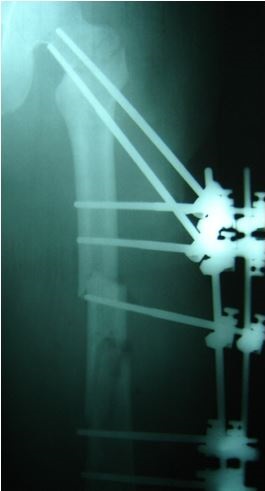

Radiografía de aplicación de ATLAS en paciente politraumatizado

El sistema de fijación permite activar todos los grados de libertad entre los elementos que conectan y es hecho con acero inoxidable y fibra de carbono lo que permite, al médico ortopedista, adaptar el tratamiento en menos tiempo y con más comodidad para el paciente, así sean posiciones complicadas.

Aunque el dispositivo está diseñado y validado para ser empleado esencialmente en pacientes con fracturas por trauma, podría utilizarse en tratamientos veterinarios, pues cuenta con pruebas biomecánicas de laboratorio y con pruebas clínicas, con resultados satisfactorios.

Entre las ventajas más significativas están su bajo costo, comparado con los demás dispositivos comerciales, así como la versatilidad para reducir fracturas o ajustar posiciones de los huesos para corregir defectos. También se destaca la estabilidad y rigidez para la formación de un buen callo óseo.